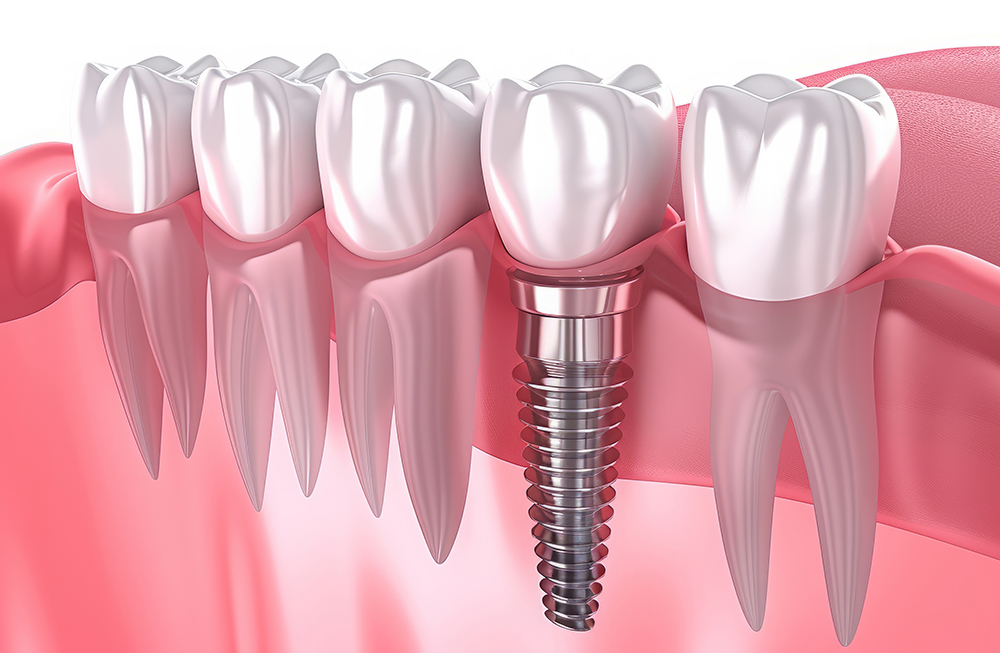

3. 임플란트 식립 수술

본격적인 임플란트 식립 과정에서는 치조골에 인공치아 뿌리(임플란트)를 심습니다. 이 과정은 국소마취를 하며, 수술 시간은 보통 한 개당 30분에서 1시간 정도 걸립니다. 수술이 끝나면 잇몸을 봉합하고, 임플란트가 뼈에 완전히 결합될 때까지 기다려야 합니다.

5. 지대주 및 보철물 부착

골유착이 완료되면 임플란트 위에 지대주(어버트먼트)를 연결하고, 그 위에 보철물을 부착합니다. 이 과정에서 환자 맞춤형 치아 모양을 디자인하고 제작하며, 자연치아와 최대한 유사하게 보이도록 조정합니다. 최종적으로 임플란트 보철물을 설치하며, 이로써 전체 시술이 마무리됩니다.